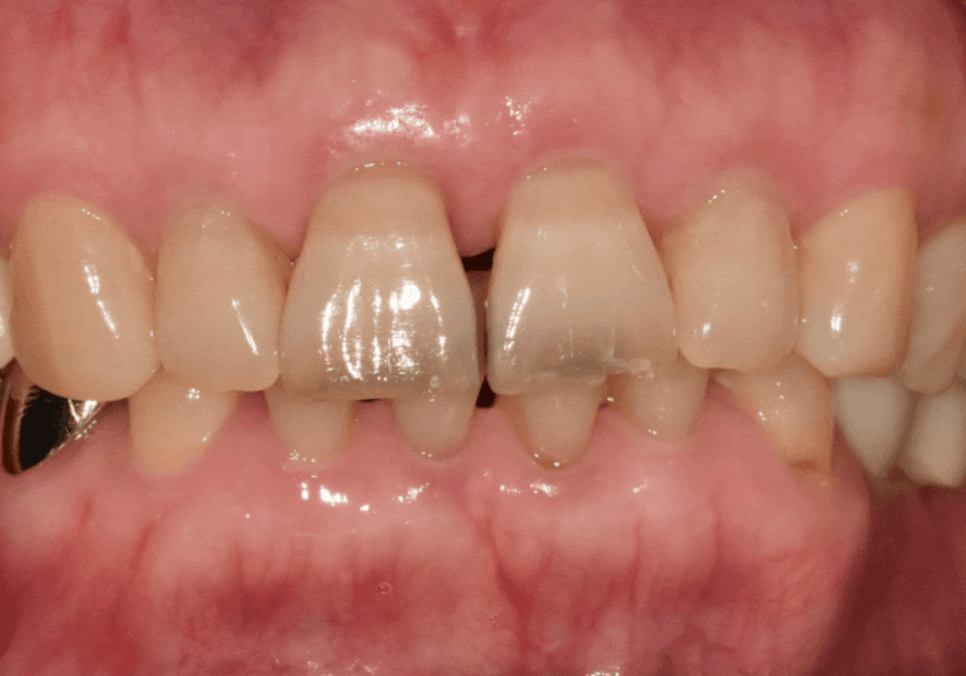

실제로 환자분의 입천장 쪽을

확인해 보니,

역시나 방어막이 사라진 마모 틈을 타

충치가 안쪽까지 깊게 퍼져 있는 모습...

다행히 충치가 신경까지 도달하지는 않아,

환자분들이 가장 무서워하시는

신경치료는 피할 수 있었습니다.